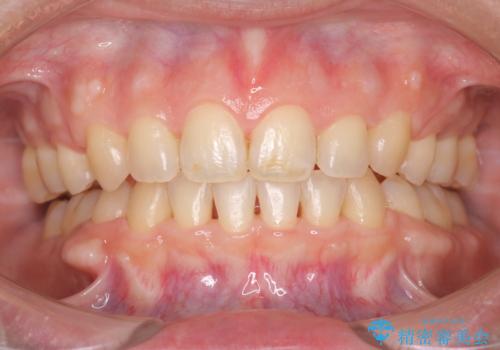

- メンテナンスの際に歯のステインが気になるということで今回はエアフローの機械を使用したクリーニングを行いました。

ステインが付着したままだと歯の表面がざらつき、普段のブラッシング時などに汚れが落ちにくくなります。定期的なメンテナンスの際にPMTC、エアフローを取り入れることをおすすめしております。